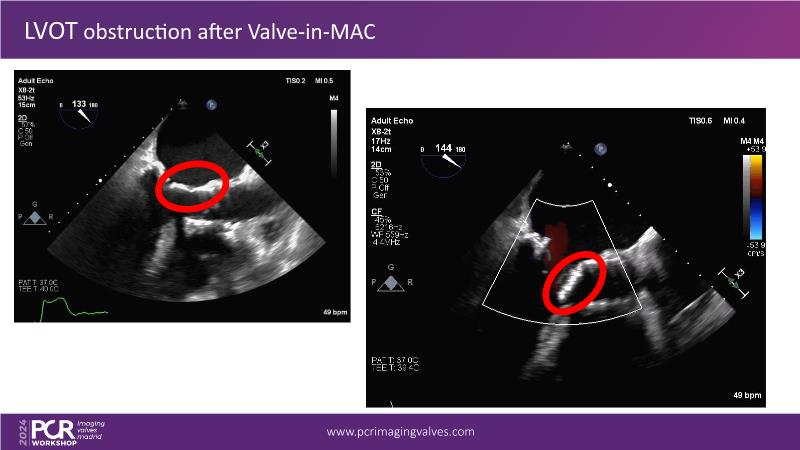

Explore cutting-edge transcatheter valve interventions for mitral and aortic valve disorders, including valve-in-valve procedures and management strategies for paravalvular leakages, and learn about diagnosing and treating mitral annular calcification and transcatheter options in infective endocarditis.

- To manage patients with mixed and multiple valvular heart disease: from risk stratification to therapeutic decision-making

- To improve management of patients with combined valvular heart disease and identify the best timing and type of treatment options

- To get tips and tricks for guidance of transcatheter intervention